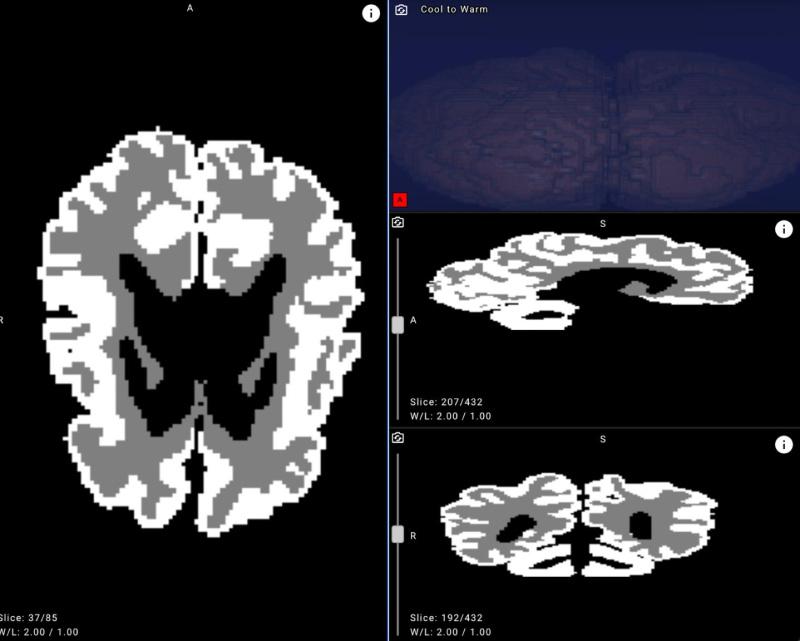

Example of an MRI brain image with white matter and gray matter masks applied after neural network processing.

To bridge this gap, Yandex researchers collaborated with medical experts to create new annotations, design a dedicated neural network architecture, and run a series of machine learning experiments. The resulting model achieved over 90% accuracy in distinguishing gray and white matter in infant brains on internal evaluation data, demonstrating its potential for clinical use.

- The proposed solution analyzes MRI scans and can distinguish between gray and white brain matter with over 90% accuracy.

- Improve accuracy and objectivity. With over 90% accuracy, the model highlights outlines and quantifies the ratio of gray to white matter in an infant’s brain.